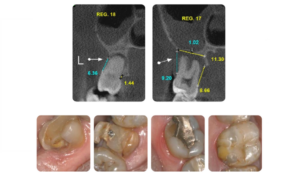

Posso dar um exemplo prático disso no caso apresentado, em que a análise mostrou uma importante interferência oclusal do terceiro molar, elemento 28, contribuindo para um basculamento articular que altera a trajetória mandibular durante o fechamento, além de uma sobrecarga excessiva que pode ter colaborado para a falha restauradora no elemento 37.

Uma vez deslocada anteriormente para possibilitar a oclusão, a mandíbula passa a fechar em uma MIH também instável, com importante interferência no elemento 17. Além de receber uma carga oclusal excessiva por ser o primeiro elemento a tocar, esse dente ainda absorve o impacto inicial de uma mandíbula que precisa se deslocar cerca de 3 mm de forma abrupta para alcançar o fechamento.

Essa leitura também permite levantar hipóteses sobre a história mecânica do caso. Considerando o padrão atual de interferências e destruição estrutural, é plausível supor que, em fases anteriores, parte dessa sobrecarga estivesse concentrada sobre o elemento 27, que hoje apresenta extensa destruição coronária.

Figura 8 e 9. Correlação entre achados tomográficos e sinais clínicos intraorais em elementos submetidos a interferências oclusais, com comprometimento estrutural e periodontal associado.